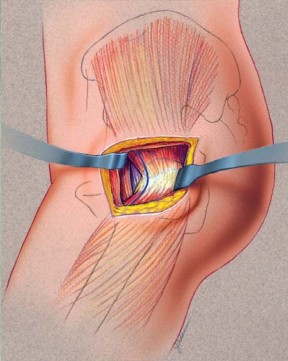

يستخدم الأستاذ الدكتور محمد هطيف تعديلًا طفيف التوغل للطريقة الجانبية المباشرة (LIDL) لضمان أفضل النتائج لمرضاه. هذه التقنية تضمن دقة عالية مع الحفاظ على الأنسجة.

وضعية المريض والشق الجراحي

يتم وضع المريض في وضع الاستلقاء الجانبي المباشر مع الجانب المراد إجراء الجراحة عليه للأعلى، والحوض عموديًا على الطاولة باستخدام دعامة صلبة. لضمان الاستقرار، يتم وضع دعامات طويلة خلفيًا عند مستوى منتصف الظهر وعند منتصف العجز، وأماميًا عند عظم القص والارتفاق العاني. يتم ثني الورك المقابل حوالي 15 درجة ويتم تبطين الشظية القريبة لمنع الضغط الزائد على العصب الشظوي المشترك. في هذا الوضع، يتم تقدير تقريبي لتساوي طول الساقين عن طريق تقييم مستوى الرضفتين والكعبين. بعد التحضير والتعقيم، يتم تحديد طرف المدور الكبير عن طريق الجس والتقييم عن طريق الجلد باستخدام إبرة نخاع شوكي.

يتم عمل شق مائل من الخلف القريب إلى الأمام البعيد، يتمركز فوق طرف المدور الكبير، ويبلغ طوله حوالي 10-12 سم للرجل متوسط الوزن (70 كجم). يتم تقليل تشريح تحت الجلد لتحديد اللفافة الأساسية إلى الحد الأدنى لمنع تكوين مساحة ميتة.